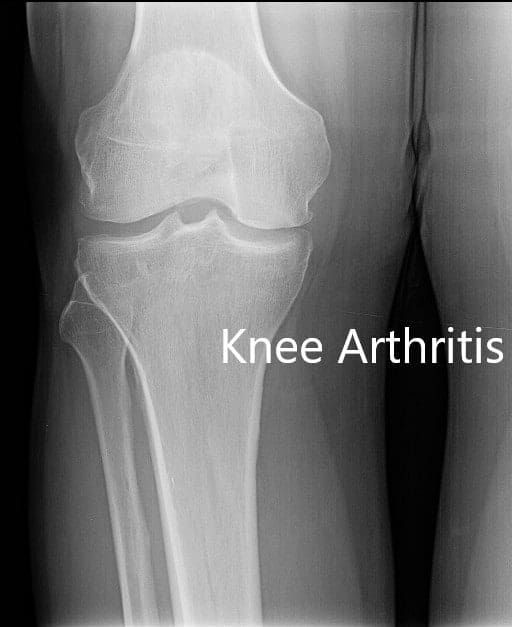

Imaging studies revealed tricompartmental osteoarthritis with degenerative changes. She was advised custom right total knee replacement considering her examination and needs. A preoperative CT was to be obtained a few weeks prior to surgery.

Preoperative X-ray showing AP and lateral view of the right knee joint, and skyline view of both the knee joints.